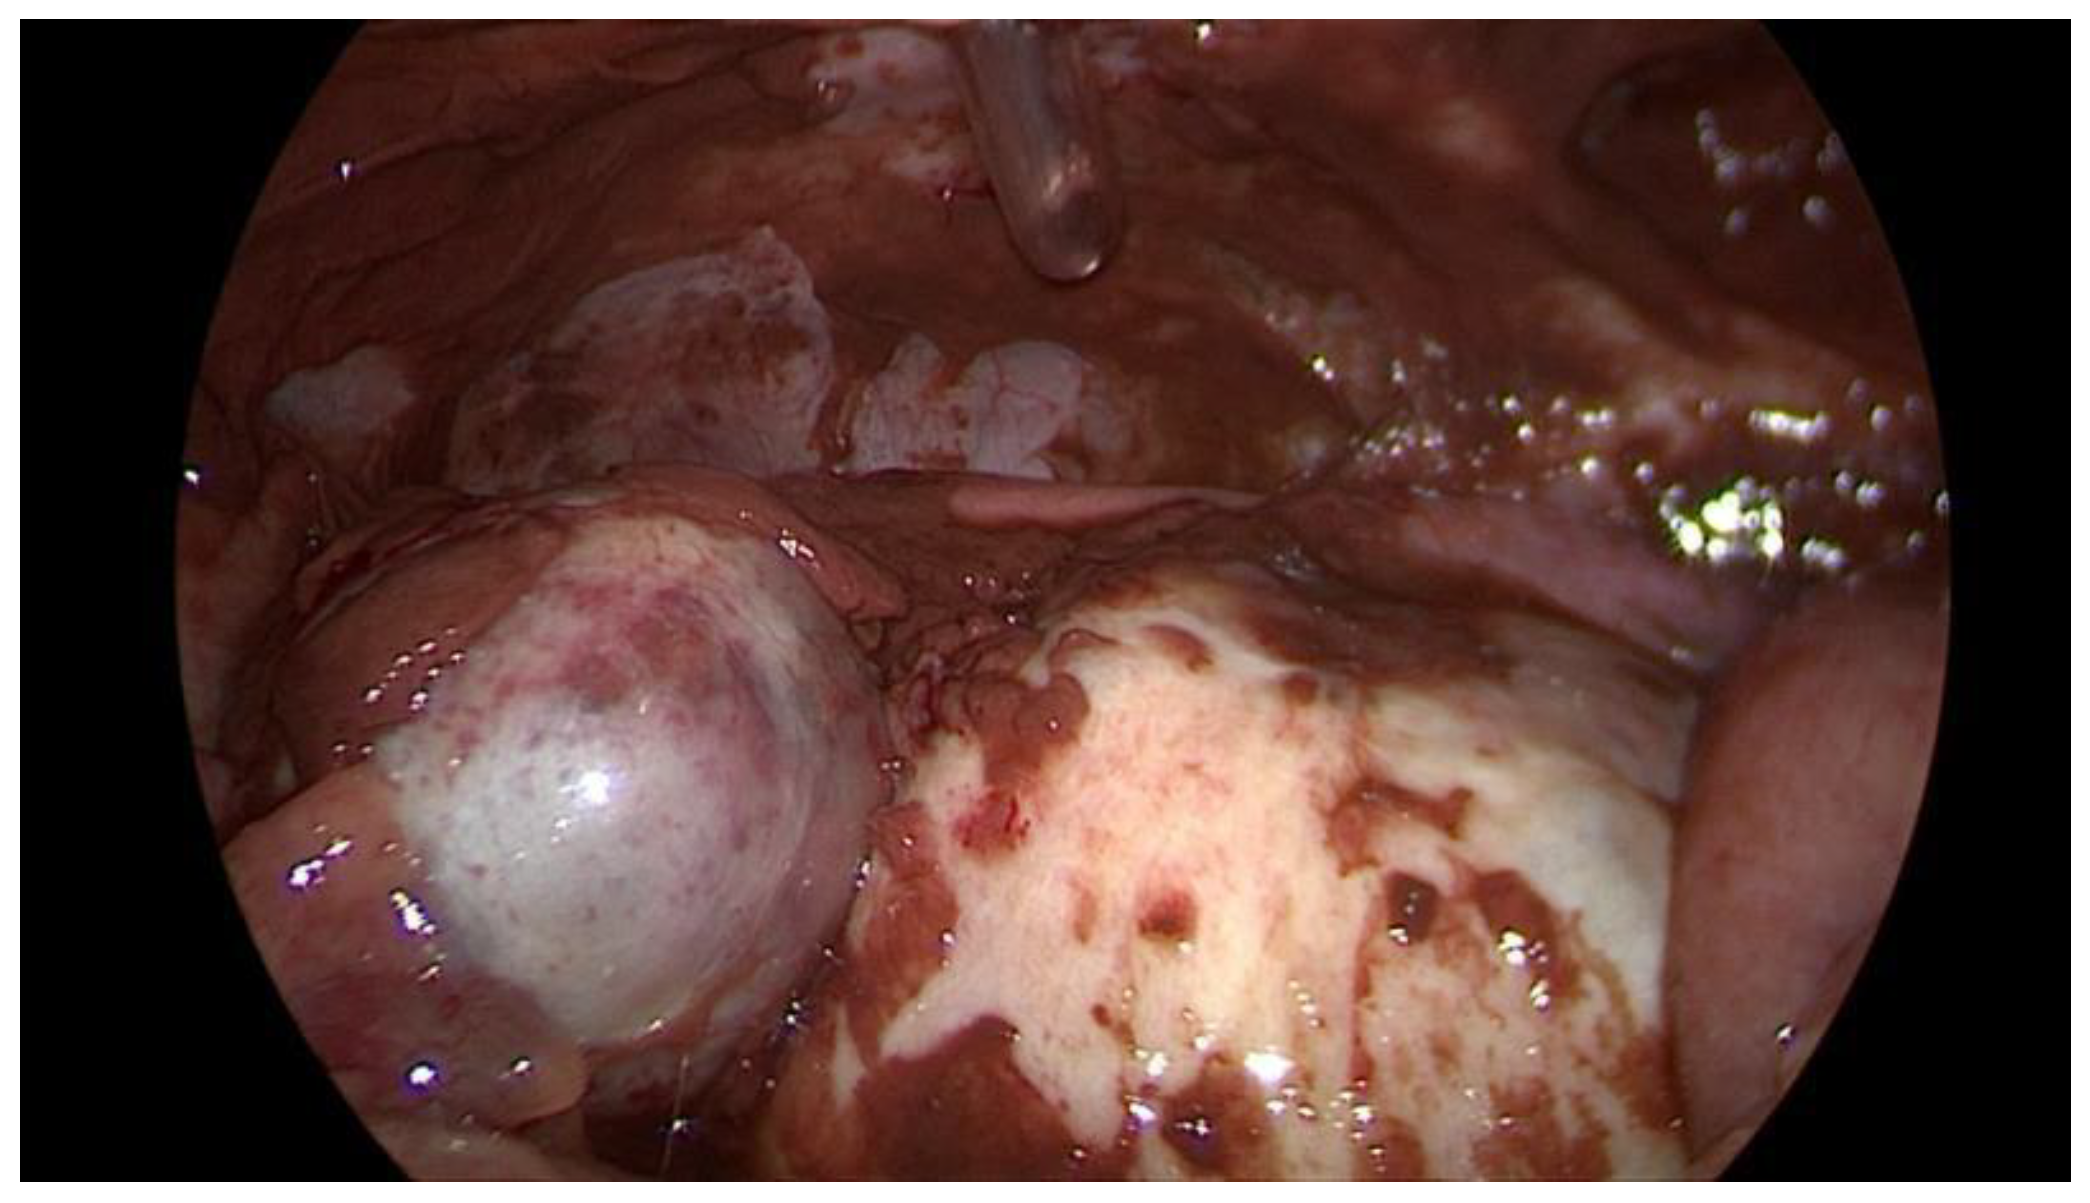

Data collection: The patients’ backgrounds, clinical symptoms at admission, sonographic and laboratory assessment, as well as intraoperative findings were recorded. Patient demographic data included age, menopausal status, presence of dysmenorrhea, history of endometriosis surgery, and use or non-use of hormonal downregulation therapy for endometriosis. Pre-operative laboratory tests included white blood cell (WBC) count, serum C-reactive protein (CRP) level, and serum CA125 level, and all patients underwent transvaginal sonography (Figure 1) on admission as part of the emergency diagnostic assessment. The maximal diameter and the location of the endometriomas were noted. The intraoperative findings included the location of the ruptured endometriomas (Figure 2 and Figure 3), the presence and classification of endometriosis according to the rASRM [16] and #ENZIAN [17] systems, and, lastly, total blood loss.

Figure 1. Sonographic display of a ruptured endometrioma of the right ovary in a 28-year-old woman with sudden onset of abdominal pain.